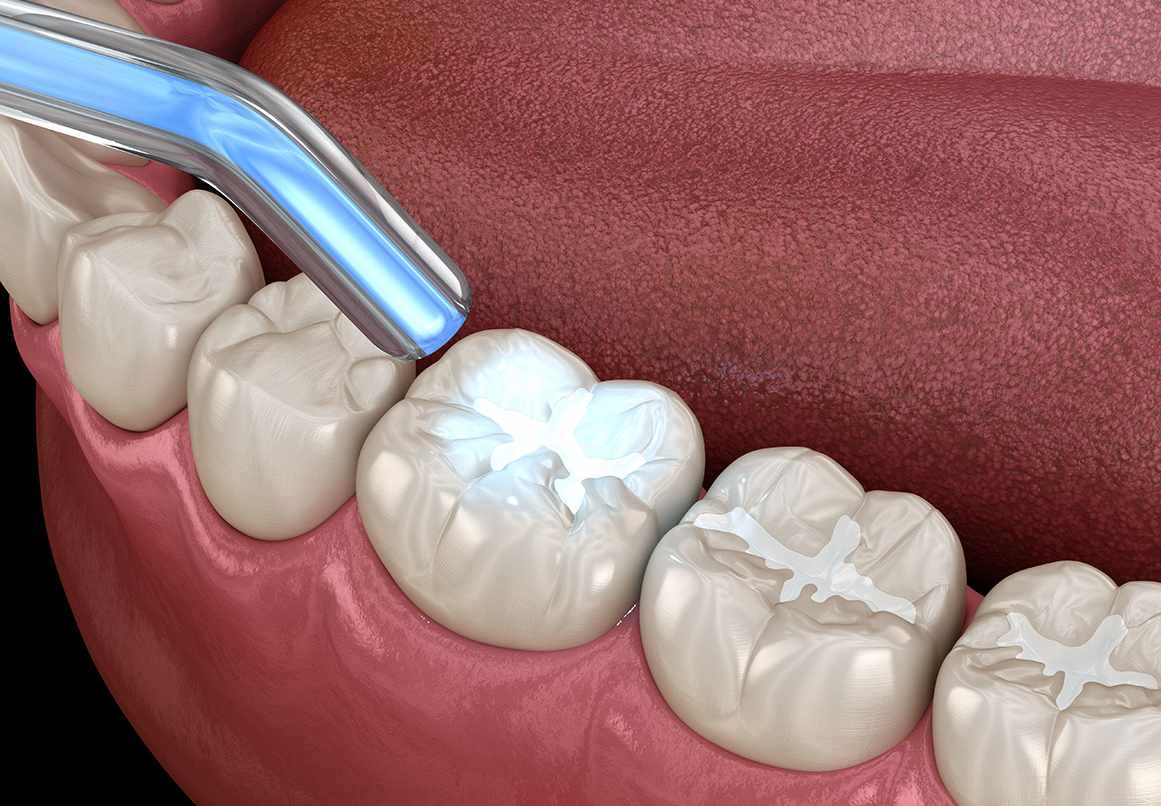

Our dentists at U Smile Family Dentistry give their patients in Mesa, AZ, several options for materials when filling cavities. However, if you are concerned about people seeing the dental work you have, then selecting composite fillings will not only protect your tooth, but many people will never see your fillings.The composite material that goes in the tooth is a combination of ceramic and plastic that produces a strong substance. The composite allows a tooth to bear up to 95 percent of the weight a natural tooth does, and it restores the patient’s ability to eat the foods they love. More people are choosing composite fillings because they blend in with natural teeth so well.Our dentists at U Smile Family Dentistry can match the composite color to the shade of your teeth. Not all teeth are perfectly white, so our dentists in Mesa, AZ, can add the tints necessary to match your teeth. If you’re interested in getting composite fillings, contact our offices for an appointment.